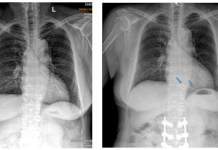

Trường hợp lâm sàng

Xử trí dị vật buồng tim: Nhân một trường hợp lâm sàng